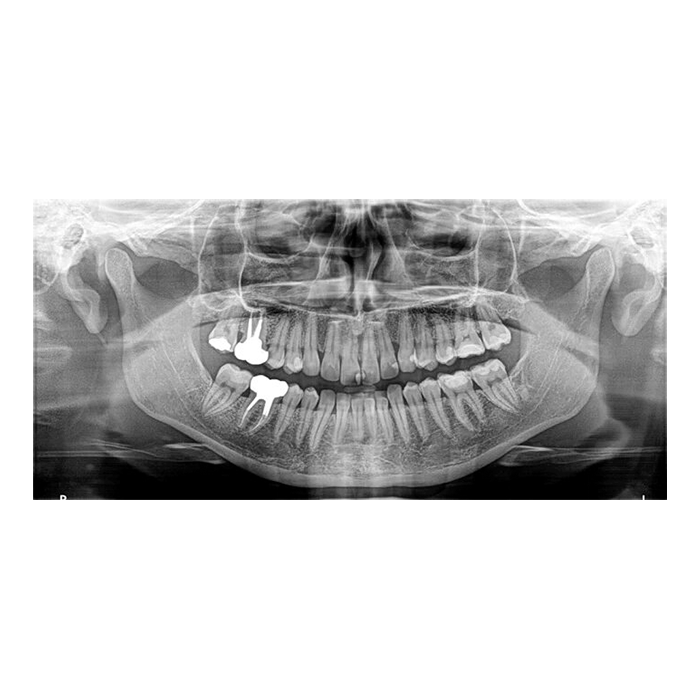

Трехмерный дентальный томограф Carestream Dental CS 8100 3D — это решение для клиник, стремящихся к высочайшему качеству диагностики при оптимальных инвестициях. Аппарат сочетает в себе проверенную надежность, интуитивно понятное управление и передовые технологии визуализации, позволяя получать детальные 3D-снимки челюстно-лицевой области.

CS 8100 3D обеспечивает полную диагностическую картину для имплантологии, хирургии, эндодонтии и ортодонтии, помогая повысить точность планирования, предсказуемость результатов и, как следствие, уровень доверия пациентов.

- Высокое качество изображений: Технология получения снимков обеспечивает отличную контрастность и разрешение, что позволяет визуализировать анатомические структуры, тонкие корневые каналы и минимальные патологические изменения.

- Имплантология: Точная оценка объема и плотности костной ткани, планирование позиции имплантатов с учетом важных анатомических структур (нижнечелюстной канал, гайморова пазуха).

- Хирургическая стоматология: Диагностика ретинированных зубов, оценка состояния ВНЧС, анализ переломов и кистозных образований.

- Эндодонтия: Обнаружение дополнительных каналов, оценка качества обтурации, диагностика перфораций и трещин корня.

- Ортодонтия: Цефалометрический анализ, оценка положения зубов и их зачатков, планирование комплексного лечения.

- Пародонтология: Визуализация уровня костной ткани вокруг зубов.